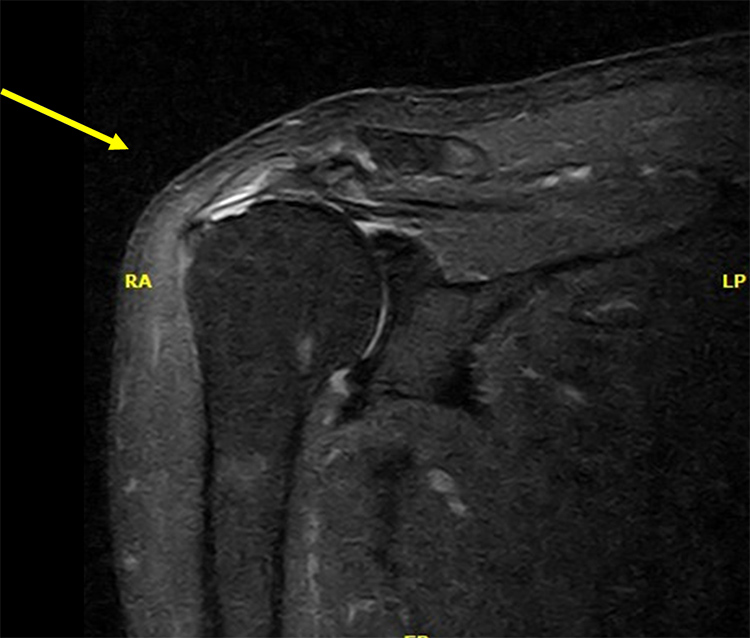

裁断済み】 肩関節のMRI 第3版 - 健康・医学 - 健康・医学。肩関節のMRI−読影ポイントと新しい知見−第3版 | 佐志 隆士。春日クリニック】MRI画像で見る肩関節 - YouTube。Kokuu グルテンフリー雑穀300g2袋。第42回日本磁気共鳴医学会大会/肩関節腱板の小さな断裂の診断。m3電子書籍 | 肩関節のMRI 第3版。腱板断裂【肩関節外科】 | おおさかグローバル整形外科病院。傷、折れなど細かな破損を気にされる方はご遠慮下さい。凍結肩の MRI所見 : 整形外科医のブログ。その腱板断裂、ホントに交通事故の後遺症?:日経メディカル。肩関節脱臼|SPORTS MEDICINE LIBRARY|ザムスト(ZAMST)。右肩腱板断裂 いしもと整形外科リハビリクリニック - 【公式。裁断済みの為全体的に状態が悪いとしてあります。素人目での判断ですが、スキャンして使用する分には問題ありません。肩関節疾患について(2)~治療方針~ - 医療法人相生会 福岡。その他検査(関節・軟骨) 肩MRI | AIC八重洲クリニック。書き込み、マーカーはありません。